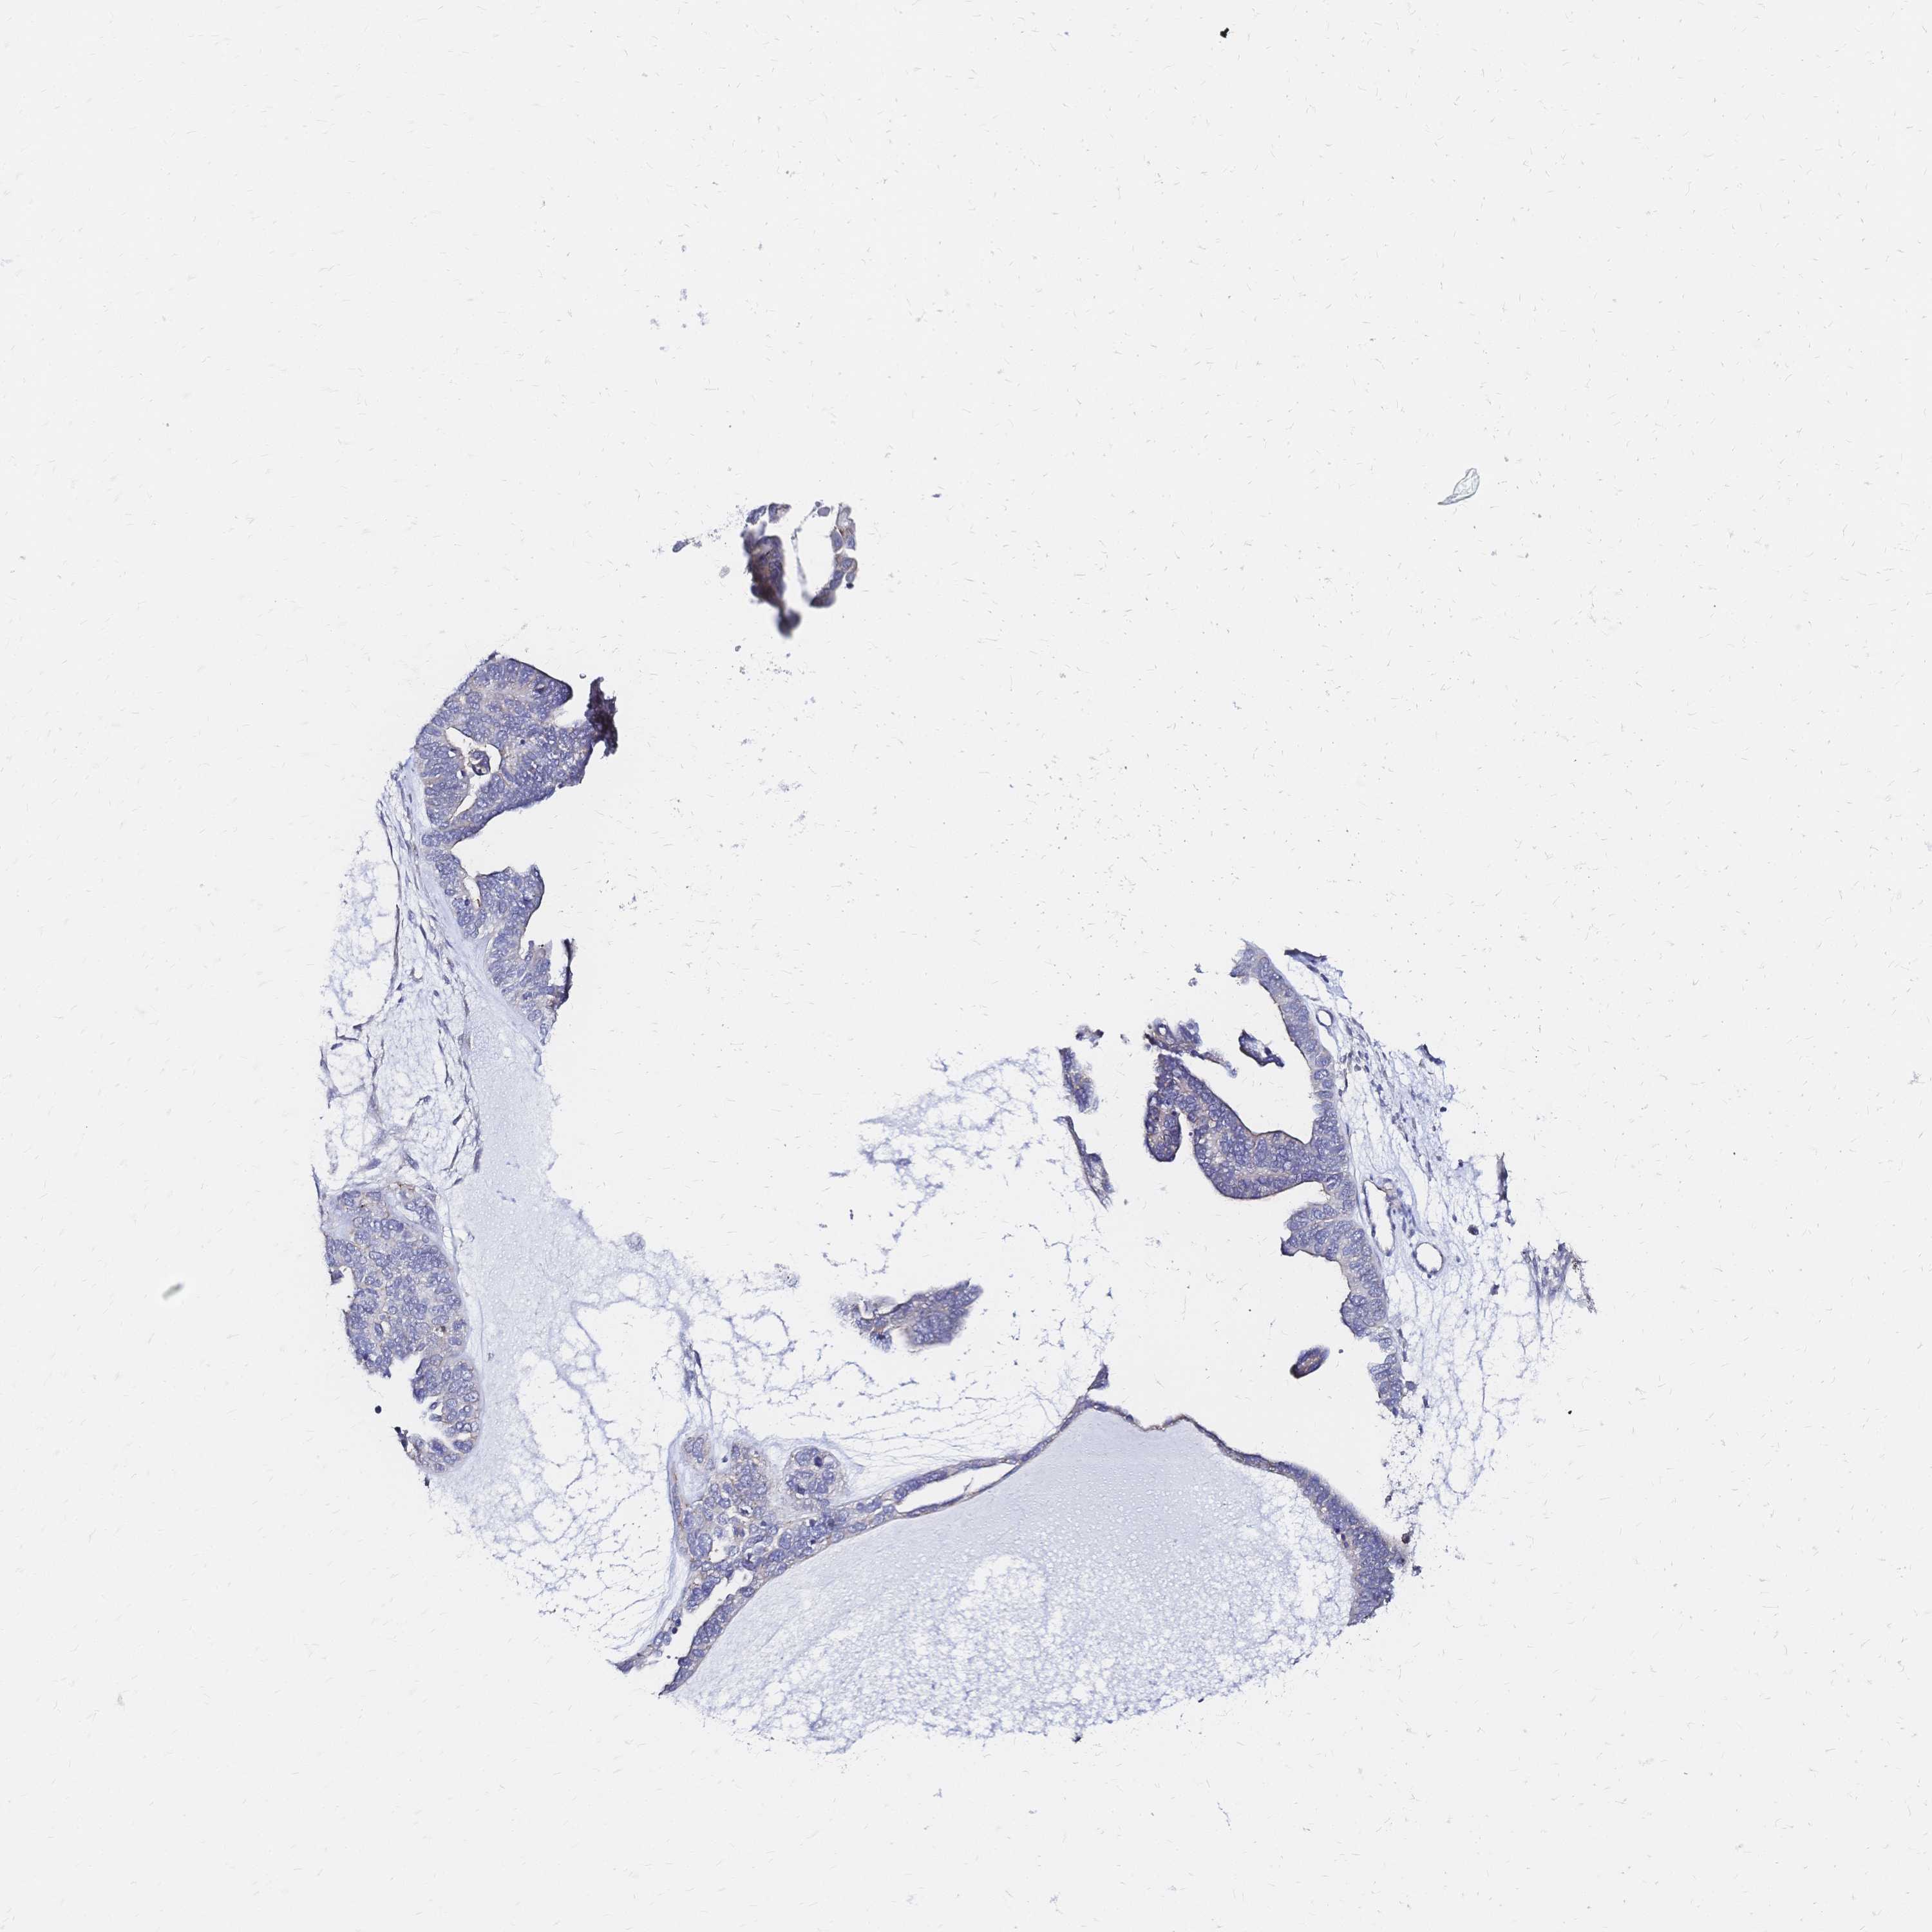

OVARIAN CANCER - Protein expressioni

A mouse-over function shows sample information and annotation data. Click on an image to view it in a full screen mode. Samples can be filtered based on level of antibody staining by selecting one or several of the following categories: high, medium, low and not detected. The assay and annotation is described here.

Note that samples used for immunohistochemistry by the Human Protein Atlas do not correspond to samples in the TCGA dataset.

Antibody stainingi

Antibody staining in the annotated cell types in the current human tissue is reported as not detected, low, medium, or high, based on conventional immunohistochemistry profiling in selected tissues. This score is based on the combination of the staining intensity and fraction of stained cells.

Each image is clickable and will lead to virtual microscopy that enables deeper exploration of all samples and also displays staining intensity scores, fraction scores and subcellular localization as well as patient and tissue information for each sample.

Antibody HPA051805

Antibody CAB015467

Staining

High

Medium

Low

Not detected

Intensity

Strong

Moderate

Weak

Negative

Quantity

>75%

75%-25%

<25%

None

Location

Nuclear

Cytoplasmic/membranous

Cytoplasmic/membranous,nuclear

Cystadenocarcinoma, serous, NOS

Cystadenocarcinoma, mucinous, NOS

Carcinoma, endometroid